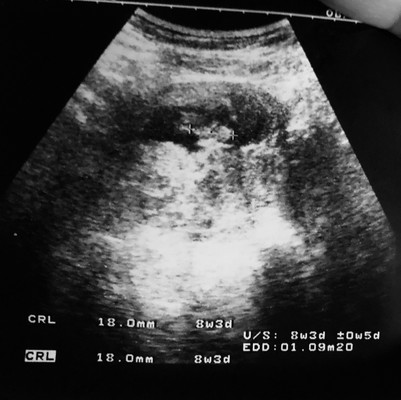

ซาวด์ครั้งแรก 9w 6d

อายุครรภ์ตามประจำเดือนไม่ตรงกับผลอัลตร้าซาวด์ค่ะ อย่างนี้จะยึดหลักไหนค่ะ